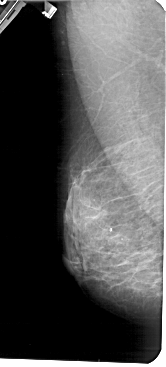

A_1425_1.LEFT_MLO

LEFT_MLO LINES 5491 PIXELS_PER_LINE 2476 BITS_PER_PIXEL 12 RESOLUTION 43.5 NON_OVERLAY